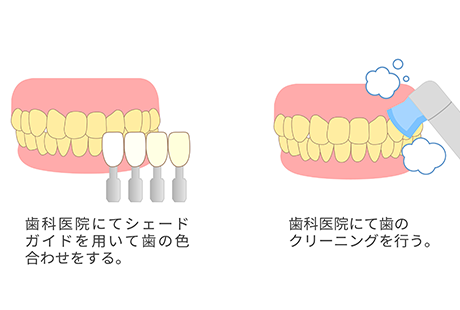

当院ではむし歯や歯周病などを未然に防ぐことを目的とし、定期的にお口の状態をチェックさせていただいております。

クリーニングなどのメンテナンスに加え、ブラッシングをはじめとする毎日のお手入れ方法もご指導いたします。健康な口腔環境を維持するとともに、異常があった場合の早期発見に繋げましょう。

歯科医師または歯科衛生士が専用の機器を用いて行う歯のクリーニングです。

歯の着色やバイオフィルムという細菌の固まりを除去することができるため、むし歯や歯周病予防にも繋がります。クリーニングのため痛みなどがなく、お口の中がスッキリします。

染め出し液で歯垢の付着状況を患者さまにもご確認いただきます。その後しっかりとセルフケアでも汚れを落とせるように分かりやすくブラッシング指導を行います。

超音波を利用して、 歯の表面や歯肉の中に付着したむし歯や歯周病の原因となる歯石や歯垢を除去します。

専用の器具とフッ素が配合された研磨剤を用いて歯の表面の汚れを除去し、磨き上げます。

最後にフッ素を歯の表面に塗布し、数分間待ちます。フッ素をしっかり浸透させるため、1時間程度は飲食やうがいはしないようにお願いします。